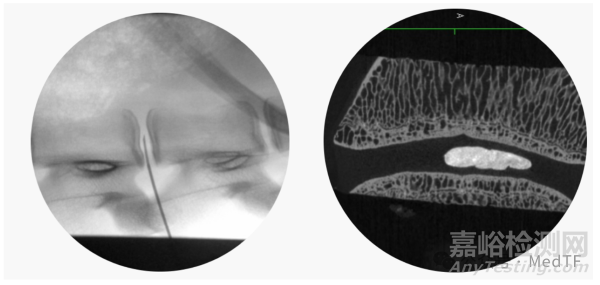

HYDRAFIL水凝膠是一種溫敏型水凝膠,該水凝膠在體外加熱可以形成如水一樣液體。可以在X射線引導下,以粘性流體狀通過17號穿刺針精準注入退變椎間盤的髓核內。

水凝膠一旦注入體內,就能與與患者的髓核組織融合,隨體溫冷卻原位固化為一體化固態(tài)植入體。

HYDRAFIL使用方式和注射位置有點類似于經皮穿刺椎體成形術(PVP),并且HYDRAFIL水凝膠與骨水泥一樣都能用于髓核增強。與骨水泥不同,HYDRAFIL水凝膠是一種富含水分的彈性材料。不僅能夠完美填充裂隙,而且能夠募集水分以恢復自然生物力學并緩解疼痛。水凝膠固化后可分散椎間節(jié)段負荷應變,改善功能并減少疼痛信號傳導。